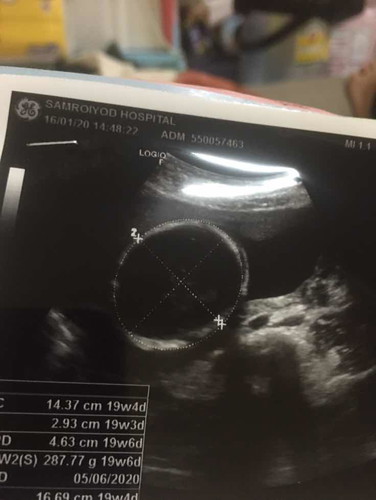

ท้องแรกค่ะไม่รู้ว่าหญิงรึชายเขาดูกันตรงไหนค่ะแม่ไไ

ต้องให้คุณหมอดูตรงอวัยวะเพศค่ะ ในรูปเป็นส่วนศรีษะ